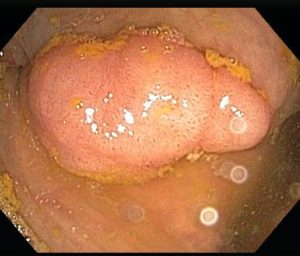

Figure 1 – Colon polyp

All of the body’s cells normally grow, divide, and then die in order to keep the body healthy and functioning properly. Sometimes this process gets out of control and cells keep growing. Colorectal polyps are abnormal growths of the inner lining of the large bowel [Figure 1]. Most commonly polyps are found in the left colon, the sigmoid colon, and the rectum [Figure 2]. Polyps can be flat (sessile polyp) [Figure 3] or can grow on a stalk (pedunculated polyp) [Figure 4]. Polyps are common but their incidence vary from country to country. In the United States of America, approximately 20 to 30% of adults have polyps. While the majority of polyps do not become cancer, some polyps are precancerous. Left untreated such polyps can turn into cancer. The size and type of polyp determine cancer risk.